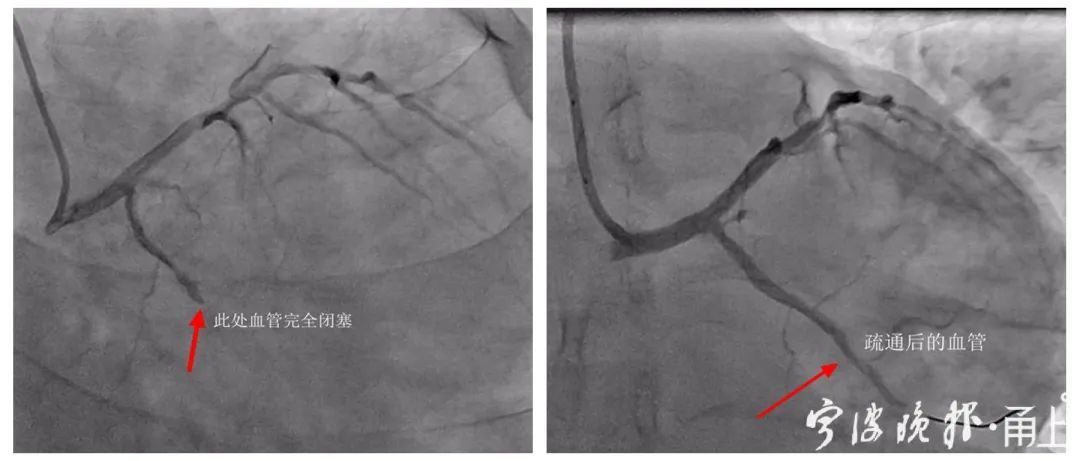

果不其然,检查过程中,医生发现小戴心脏内冠状动脉的回旋支已是完全闭塞状态,随时可能有生命危险。

考虑到小戴还很年轻,两位专家征得患者及家属同意后,决定暂不放置支架,先通过球囊扩张术开通闭塞的血管。

短短20多分钟后,手术顺利完成,小戴各项生命体征逐渐恢复。经过近一周的后续治疗,日前小戴已康复出院。

血管疏通前后。